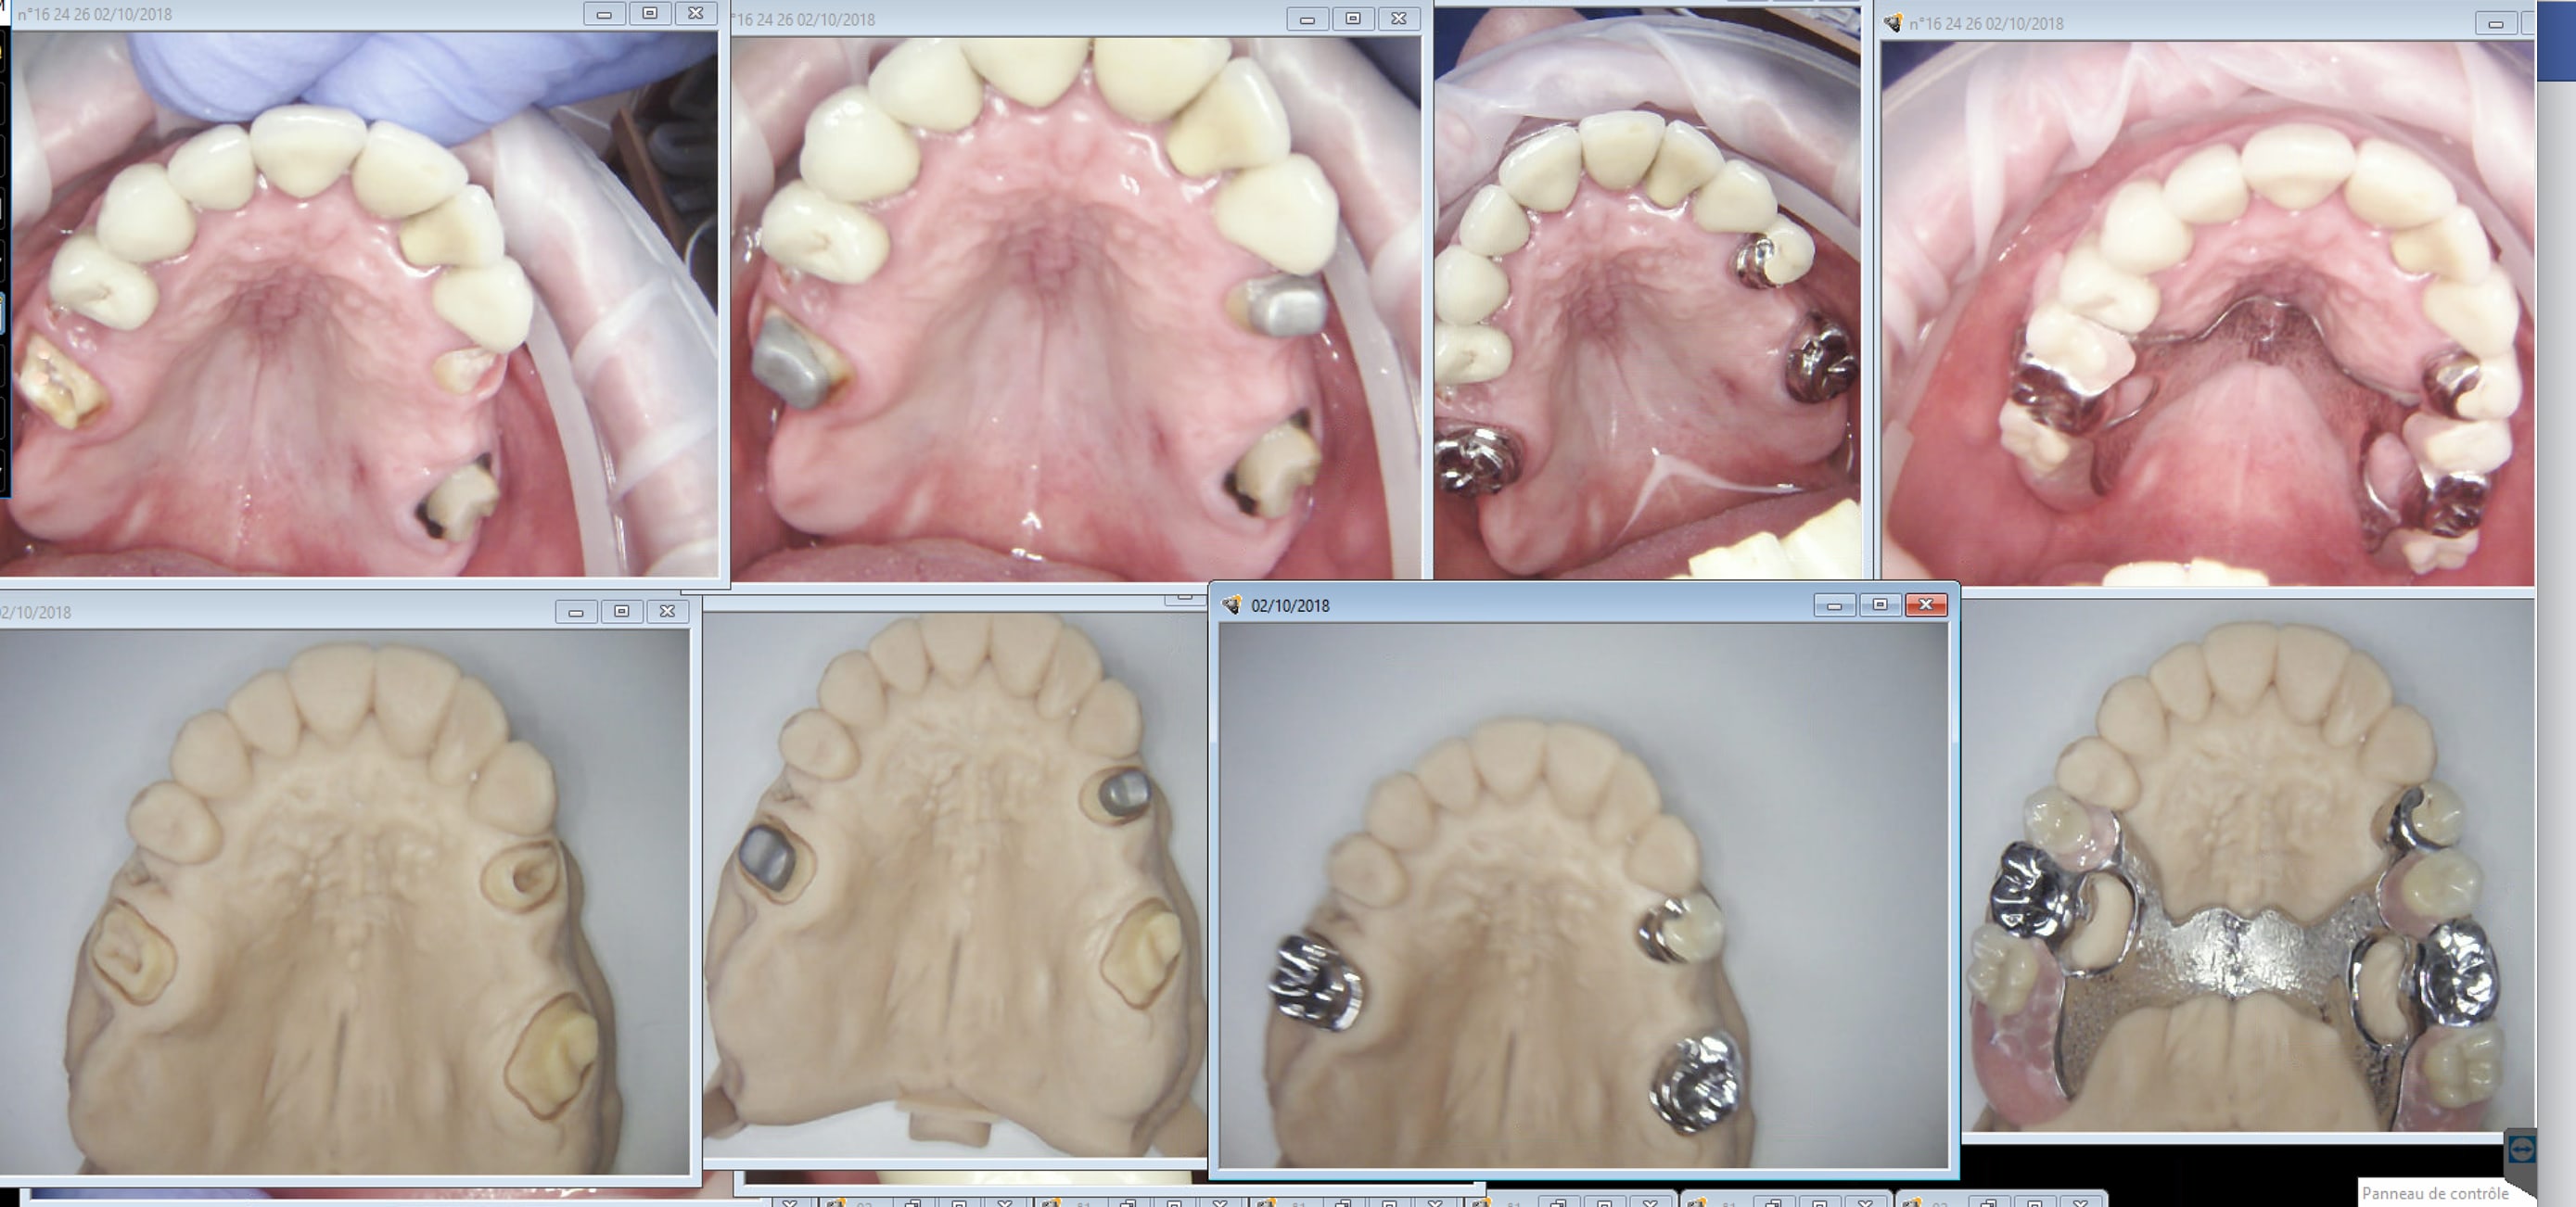

ces réalisation low cost ne sont pas à mettre à l'honneur ni de la partielle ni des des réalisations CAD CAM .....

la partielle vaut mieux que cela ....

à titre d'informations complémentaires

1. les modèles présentés sont MADE IN FRANCE

les derniers cas montrent que cela ne s'améliore pas .....

Effectivement. De la daube. Ces glands m'ont meme fait de la fixe en meme temps qu'une finition directe du stellite. -)))

Je ne vois pas bien le rapport entre CAD CAM et stelitte de merde !

Log69 tu voudrais dire que la gestion numérique des empreintes et de la conception de ce type de prothèse serai codée pour fournir de la merde, photos à l'appui comme preuve?

La prothése partielle à châssis métallique est un domaine plutôt délaissé dans la formation continue et pas mal de nos confrères ne s'y intéressent pas le moins du monde, et au final les prothésistes suivent la demande: simple et pas cher, le CAD CAM va encore simplifier cette situation par l'amélioration des empreintes et des enregistrements inter maxillaire. Simplification extrême puisque la précision d'une finition direct issue d'une seule empreinte est époustouflante. Mais si la demande et la formation des praticiens n'évolue pas vers une conception de châssis et supports plus abouti, il n'y a pas de raison pour que la qualité progresse.

Ton constat n'a rien à voir avec la CAD CAM (bien au contraire), mais avec le désintérêt de notre profession pour ce type de prothèse,

Je comprends pas bien l'intérêt de tes posts.

Tu balances une photo d'un modèle et ...... rien.

Sur un autre post, tu balance une pano et ........rien.

Y'a rien qui suis, pas de démarche clinique, pas d'objectif thérapeutique, pas de truc de dentistes quoi.

Et pis évaluer la qualité d'une prothèse sur un modèle en plâtre, comment dire....

1. il est facile de voir les insuffisances des réalisations, absence d'appuis et donc de logettes, conceptions erronées, ...

2. ce constat s'applique à toutes les prothèse faites de façon conventionnelle ou en CAD CAM

3. le CAD CAM aggrave la situation car toutes ces prothèses sont réalisées sans tracé préalable et donc sans préparation de la bouche, ce qui est la négation de la partielle